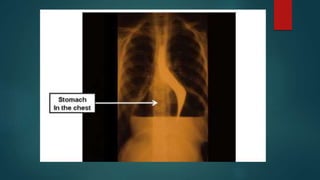

 A hiatal hernia can be diagnosed with a specialized X-ray (using a

barium swallow) that allows a doctor to see the esophagus,

 or with endoscopy.